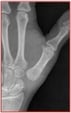

Le diagnostic repose sur la clinique. Les radiographies de face et de profil de l’articulation trapézo-métacarpienne (T-M) sont nécessaires pour confirmer le diagnostic, établir le stade de l’arthrose et dans certains cas faire le diagnostic différentiel avec l’arthrose péritrapézienne qui peut toucher toutes les surfaces articulaires du trapèze.

La rhizarthrose est très fréquente et de plus en plus mal tolérée surtout pendant les poussées inflammatoires douloureuses. Même si cette douleur reste localisée à la base du pouce, elle rend difficile les gestes de la vie quotidienne comme serrer une clé, ouvrir un bocal ou peler un fruit… ces douleurs peuvent devenir permanente, responsable de raideur et de gonflement. Par la suite vont apparaître des déformations avec des subluxations de la base du 1er métacarpien avec des retentissements sur la 1ère commissure en la refermant et une exploitation exagérée de la MP provoquant son extension pour aboutir à la déformation caricaturale du pouce en Z de chiffre (photo)